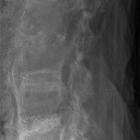

chalk stick fracture

Chalk stick, also known as carrot stick fractures, are fractures of the fused spine, classically seen in ankylosing spondylitis.

They usually occur through the disco-vertebral junction in the lower cervical or upper thoracic spine.

Not surprisingly, it is named because of the resemblance of the fracture to breaking a chalk stick or a carrot.